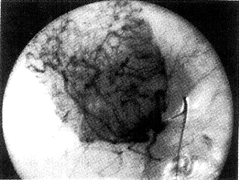

图4 X线数字减影肝动脉造影动脉期,肝右叶肿瘤血供丰富,肿瘤血管呈近似放射状分布

4.血管造影表现:肿瘤均呈富血供型,供血动脉明显增粗、迂曲,肿瘤血管从周边向中央分布,呈近似梳齿状或放射状2例(图4),肿瘤血管粗细不均4例,粗细较均2例,肿瘤区肝静脉早期显影4例,未见动-静脉瘘。